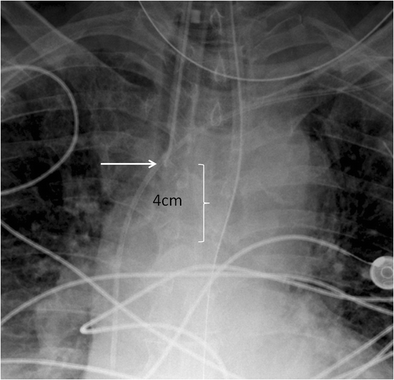

figure 7

Cropped chest radiograph image centered on the carina. The ET tube tip is low at the orifice of the right main stem bronchus (white arrow)